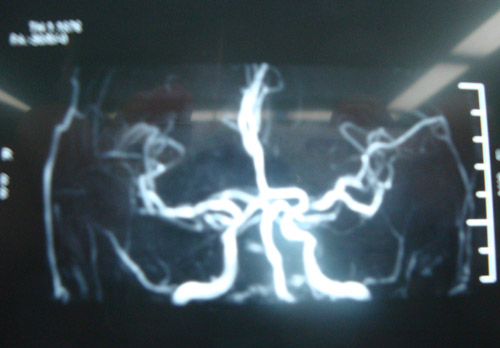

DSA示:双侧颈内动脉球部、虹吸部狭窄;左侧椎动脉近端闭塞,右侧椎动脉全程串珠样狭窄。

胃大部切除术后

该患者为老年男性,有高血压病史,以“后循环症状(反复头晕)”就诊,右侧基底节区陈旧性梗塞灶。造影及DSA检查证实其双侧颈动脉狭窄(右侧重),远端虹吸段亦存在狭窄;右椎动脉串珠样改变。因椎动脉呈串珠杨改变,无法进行手术操作。因此,建议通过手术取出颈动脉病变,改善脑部整体供血,既可避免中风发作,又可以通过侧枝循环改善后循环,缓解头晕症状。

2010年10月20日,由协作组张勤奕教授和宁新宇教授前往南华大学附二院为其顺利实施右侧颈动脉内膜剥脱术。术后患者情况稳定,未出现任何并发症。